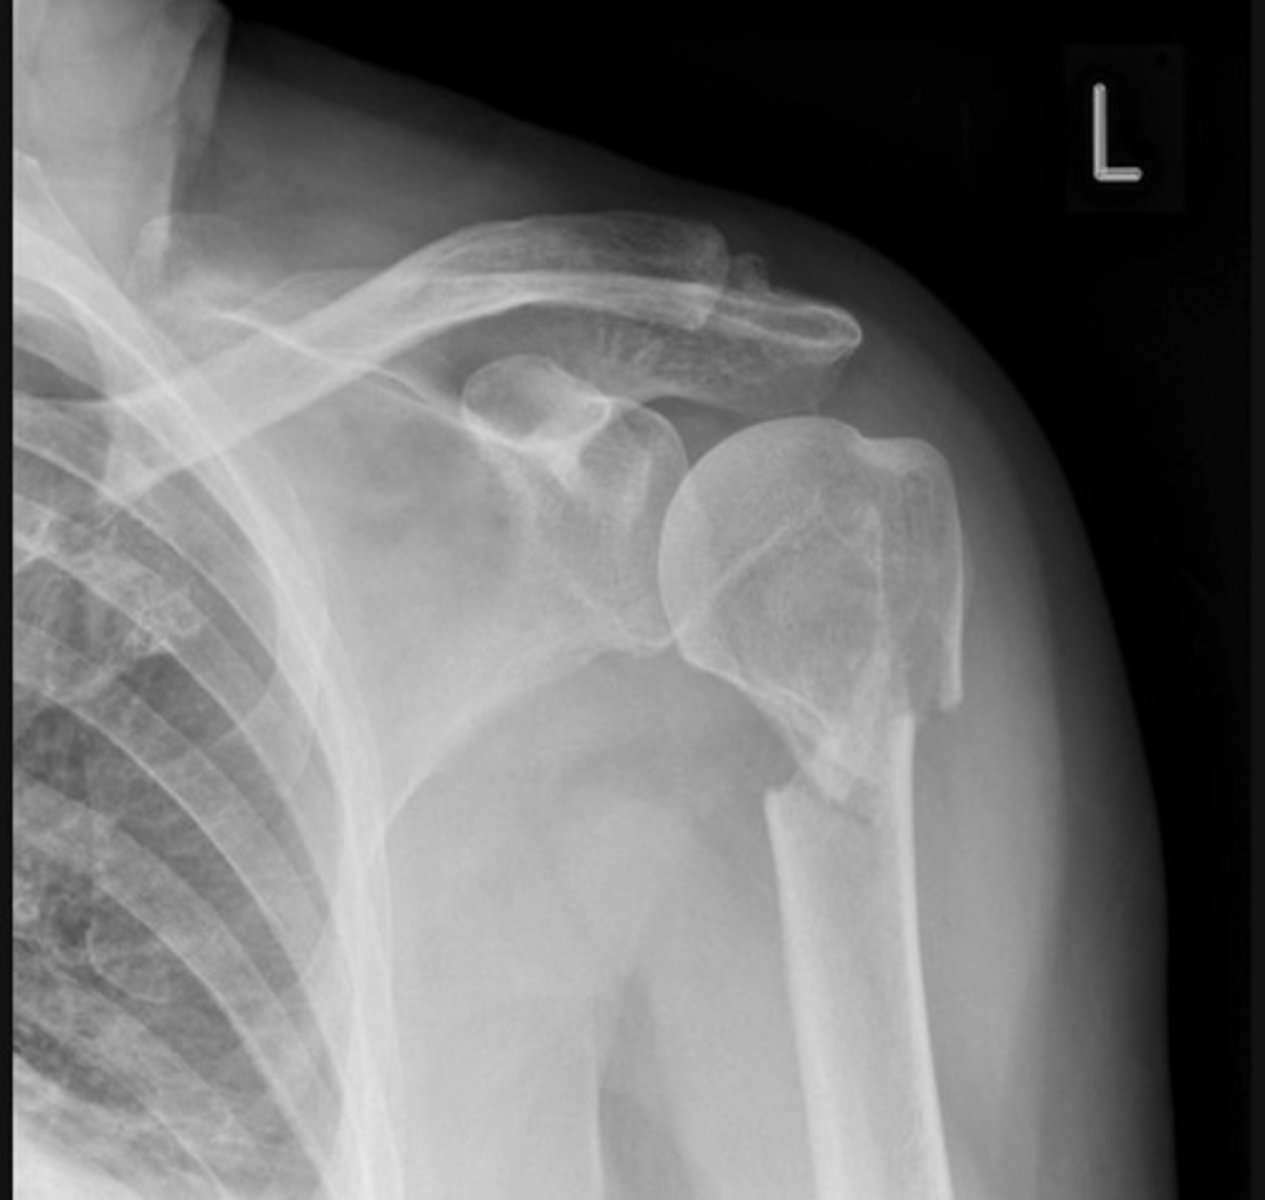

Anterior dislocation and Hill-Sachs lesion

Anterior dislocation and glenoid fracture (bankhart lesion)